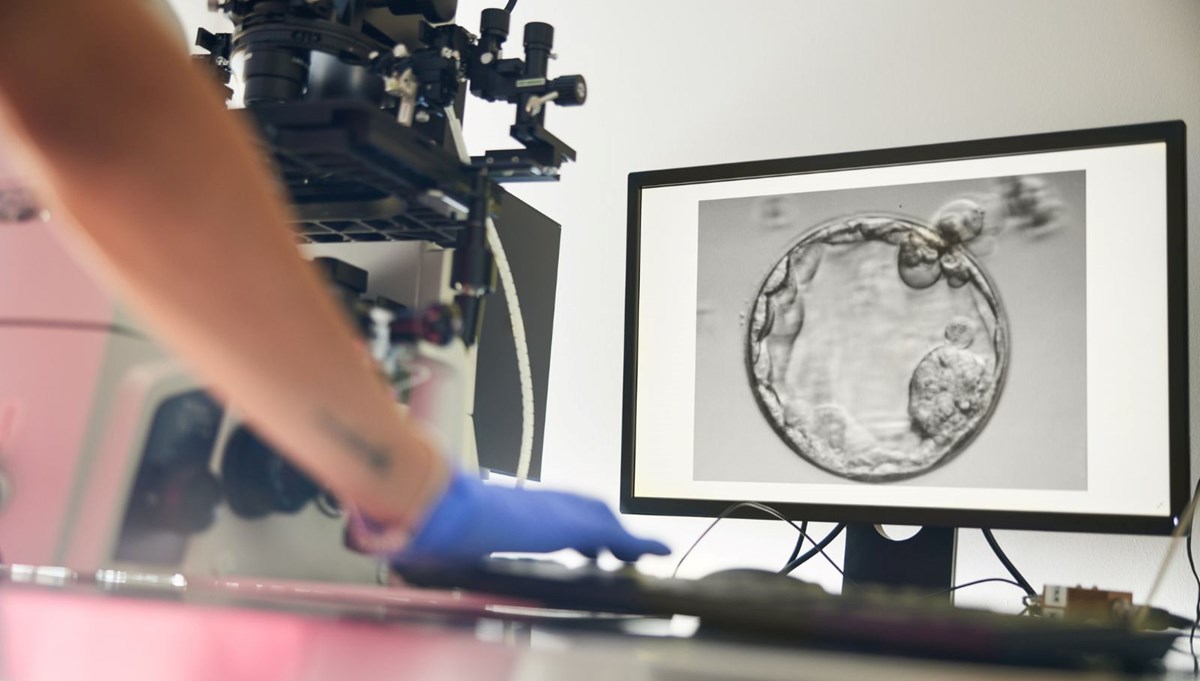

Bilim insanları, insan derisi hücrelerinden döllenebilir yumurta üretmeyi başardı. Henüz erken aşamada olan bu gelişme, gelecekte kısırlık tedavisinde yeni umutlar sunabilir.

Nature Communications dergisinde yayımlanan araştırmada, bilim insanları sıradan bir insan deri hücresinin çekirdeğini (genetik bilginin büyük bölümünü taşıyan yapı) alıp, çekirdeği çıkarılmış bir donör yumurtaya aktardı.

Bu yöntemle 82 işlevsel insan olgunlaşmamış yumurta hücresi üretildi ve laboratuvar ortamında döllenme sağlandı.

Ortaya çıkan yumurta, deri hücresini sağlayan kişiyle genetik olarak akraba oluyor ve başka bir bireyin spermiyle döllenebiliyor. Araştırmacılar bunun kısırlık tedavisinde yeni bir kapı aralayabileceğini vurguluyor.